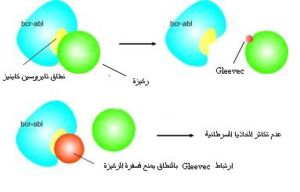

- إيمينتاب Imintab Mesylate (الإسم التجاري Gleevec أو Glivec)

يعمل هذا الدواء كمثبط لنطاق أدينوسين ثلاثي الفوسفات الموجود في الإتحاد الجيني ABL-BCR لمنع فسفرة أو نقل إشارة للجزيئات الأخرى. أظهرت الأبحاث أن أكثر من 80% من المرضى أظهروا عدم وجود لكروموسوم فيلادلفيا في الخلايا السرطانية. من الأعراض الجانبية للعلاج غثيان و صداع و طفح جلدي و آلام في العظام و تسمم خلايا الكبد و يظهر ذلك بارنفاع أنزيمات الكبد.